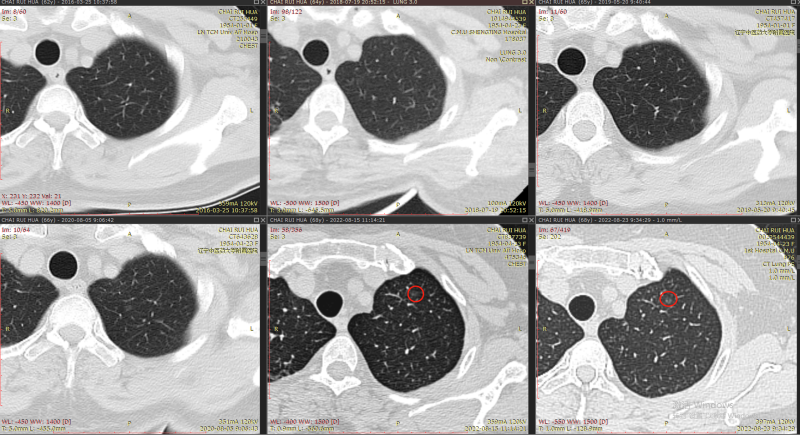

肺部情况:9年前首次发现肺结节,大夫让定期观察,之后每年做一次肺ct,今年6、7月份患者首次接种新冠肺炎疫苗2针剂,7月份患者在中医院体检时接到医院电话,提示肺部结节较以往有增大(以往近五年是0.8,今年是0.9*1.0),肺部有炎症,让进一步确诊。

2022.7.26-8.05日在中医院住院输液头孢8天消炎,8月5日高分辨率CT复查,大夫说通过高分辨CT发现磨玻璃结节上有毛刺,不太好,让到省内权威的中国医大一院复诊,8.23日中国医大一院让在本院做64排薄层ct,大夫说我母亲肺结节为多发,从这么多年看,结节发展较慢,惰性较强,可以先用拜复乐消炎,2个月后复查肺CT和CEA、NSE、肺癌7抗体的血液检查。

结节1:

2013年

2016年-2022年

右肺下叶背段纯磨玻璃结节,最大截面约0.9cm×0.9cm,平均CT值约-431Hu,结节呈类圆形,其中可见小空泡,病灶边界清楚,与9年前CT片比较,病灶密度、大小均无明显变化,考虑为微浸润性腺癌-浸润性腺癌,以微浸润性腺癌可能性大。

本次阅片我们用了2个多小时进行了比较:其余结节通过9年的比较,均未见明显高风险,手术可以不用处理。